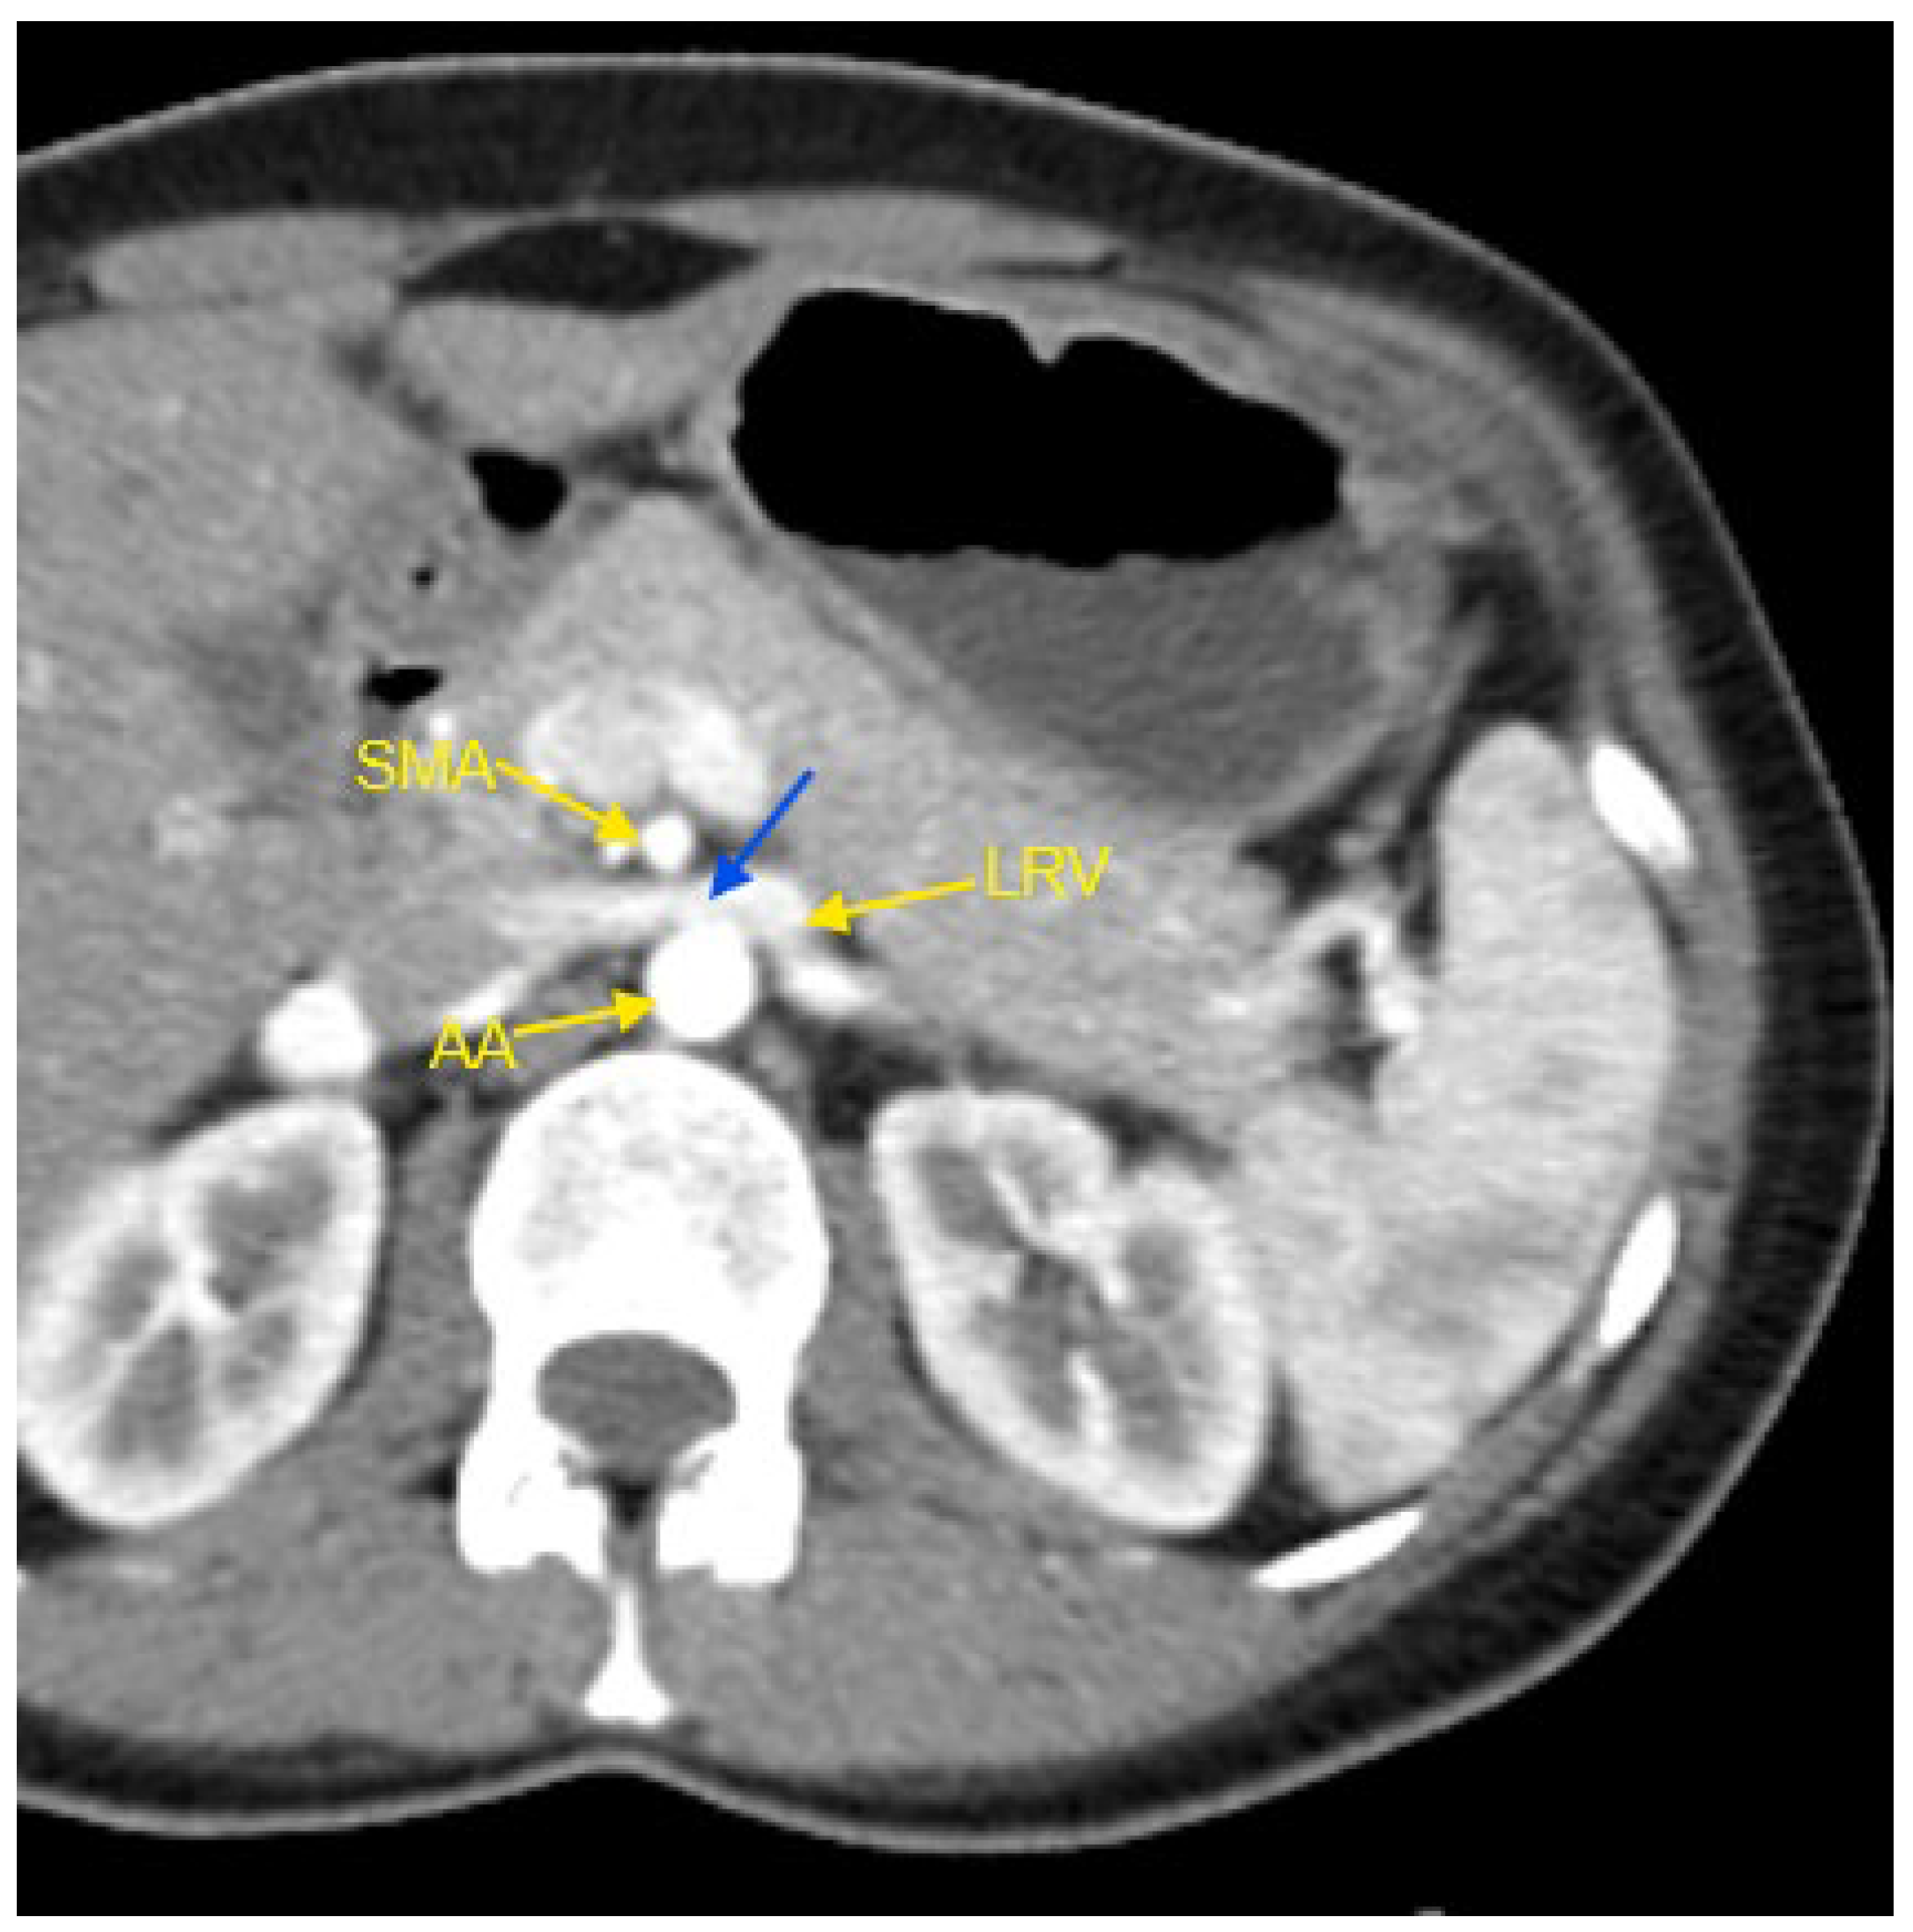

Figure 1. Contrast-enhanced CT imaging of a 44-year-old female patient with high blood pressure refractory to treatment, revealed characteristic findings consistent with classic Nutcracker syndrome. In the presented image, the abdominal aorta, the superior mesenteric artery, and the left renal vein are indicated by yellow arrows. The compressed segment of the left renal vein is highlighted by a blue arrow. AA—abdominal aorta; CT—computed tomography; LRV—left renal vein; SMA—superior mesenteric artery.